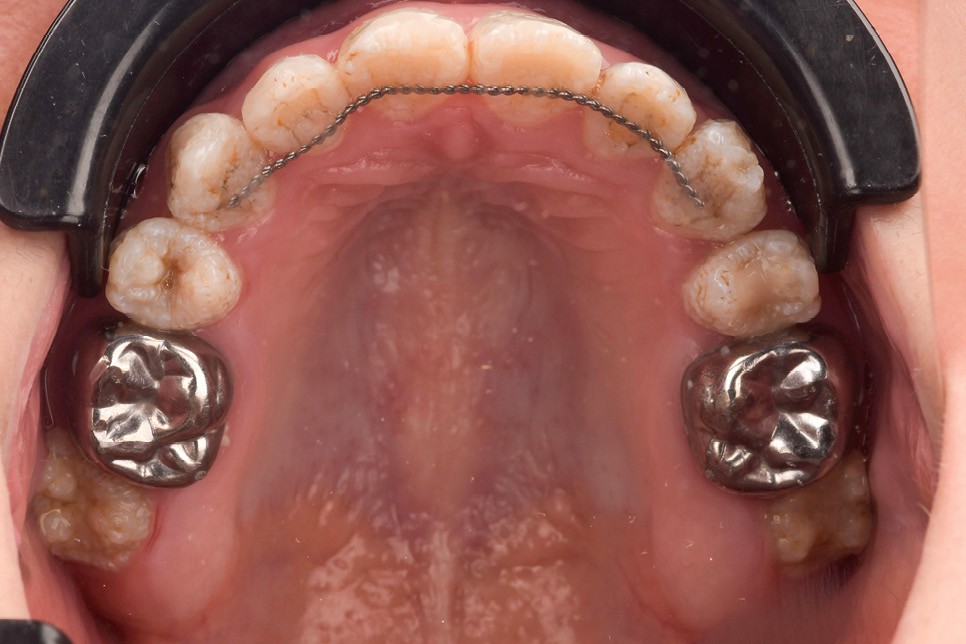

Lors de l’arrivée de la patiente, un examen clinique au fauteuil est effectué, complété par une empreinte numérique permettant l’enregistrement précis des arcades dentaires et de l’occlusion existante. Cet examen initial met en évidence une pathologie de type amélogenèse imparfaite. On note également la présence de couronnes métalliques au niveau des premières molaires, ainsi que de multiples restaurations, notamment au niveau des dernières molaires (fig. 1 à 4).